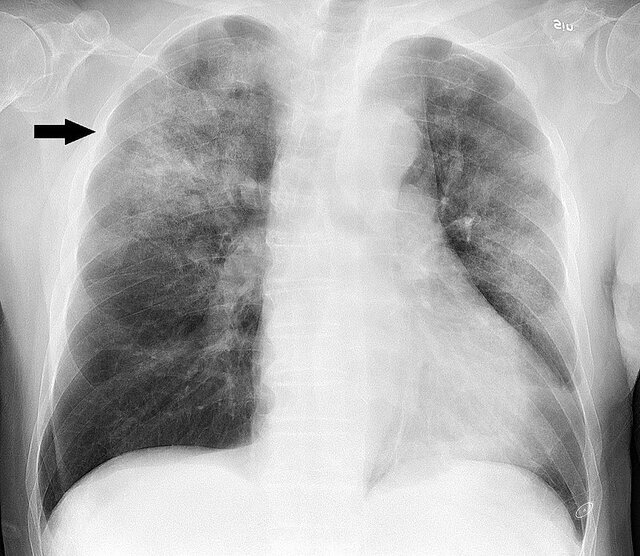

ویروس سینسیشیال تنفسی (RSV) به راحتی از طریق سرفه و عطسه منتشر میشود و تقریبا همه کودکان تا دو سالگی به آن مبتلا میشوند. در کودکان بزرگتر و بزرگسالان، این ویروس ممکن است باعث سرفه یا سرماخوردگی شود اما در خردسالان می تواند باعث برونشیولیت (نوعی التهاب ریوی) شود که دلیل اصلی مراجعه کودکان زیر پنج سال به بیمارستان است.